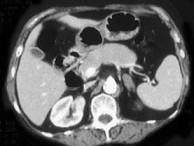

问题 女,42岁,夜尿增多伴高血压,实验室检查:血和尿醛固酮水平增加,请结合图像,选择最佳答案()

选项 A.双侧肾上腺增生 B.双侧肾上腺腺瘤 C.双侧肾上腺未见异常 D.双侧肾上腺转移瘤 E.双侧肾上腺淋巴瘤

答案 A